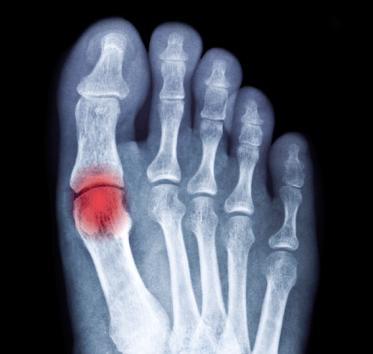

The risk of gout increases with age, and it is thus more common in ageing populations. Gout results from sustained elevation of serum urate levels (hyperuricaemia). Urate levels may increase due to diet, genetic predisposition and environmental factors leading to the deposition of monosodium urate crystals, which triggers recurrent episodes of pronounced acute inflammation, known as gout flares. Gout leads to substantial morbidity, severe pain, reduced quality of life, decreased physical function, increased healthcare costs, and lost economic productivity. In some patients a conglomerate of inflammatory cells and monosodium urate form Tophi, which can form on joints, tendons and other soft tissue, which can cause pain and deformation. Furthermore, gout is strongly associated with a number of comorbidities, including hypertension, cardiovascular disease, renal impairment, diabetes, obesity, hyperlipidaemia and frequently in a combination known as the metabolic syndrome.